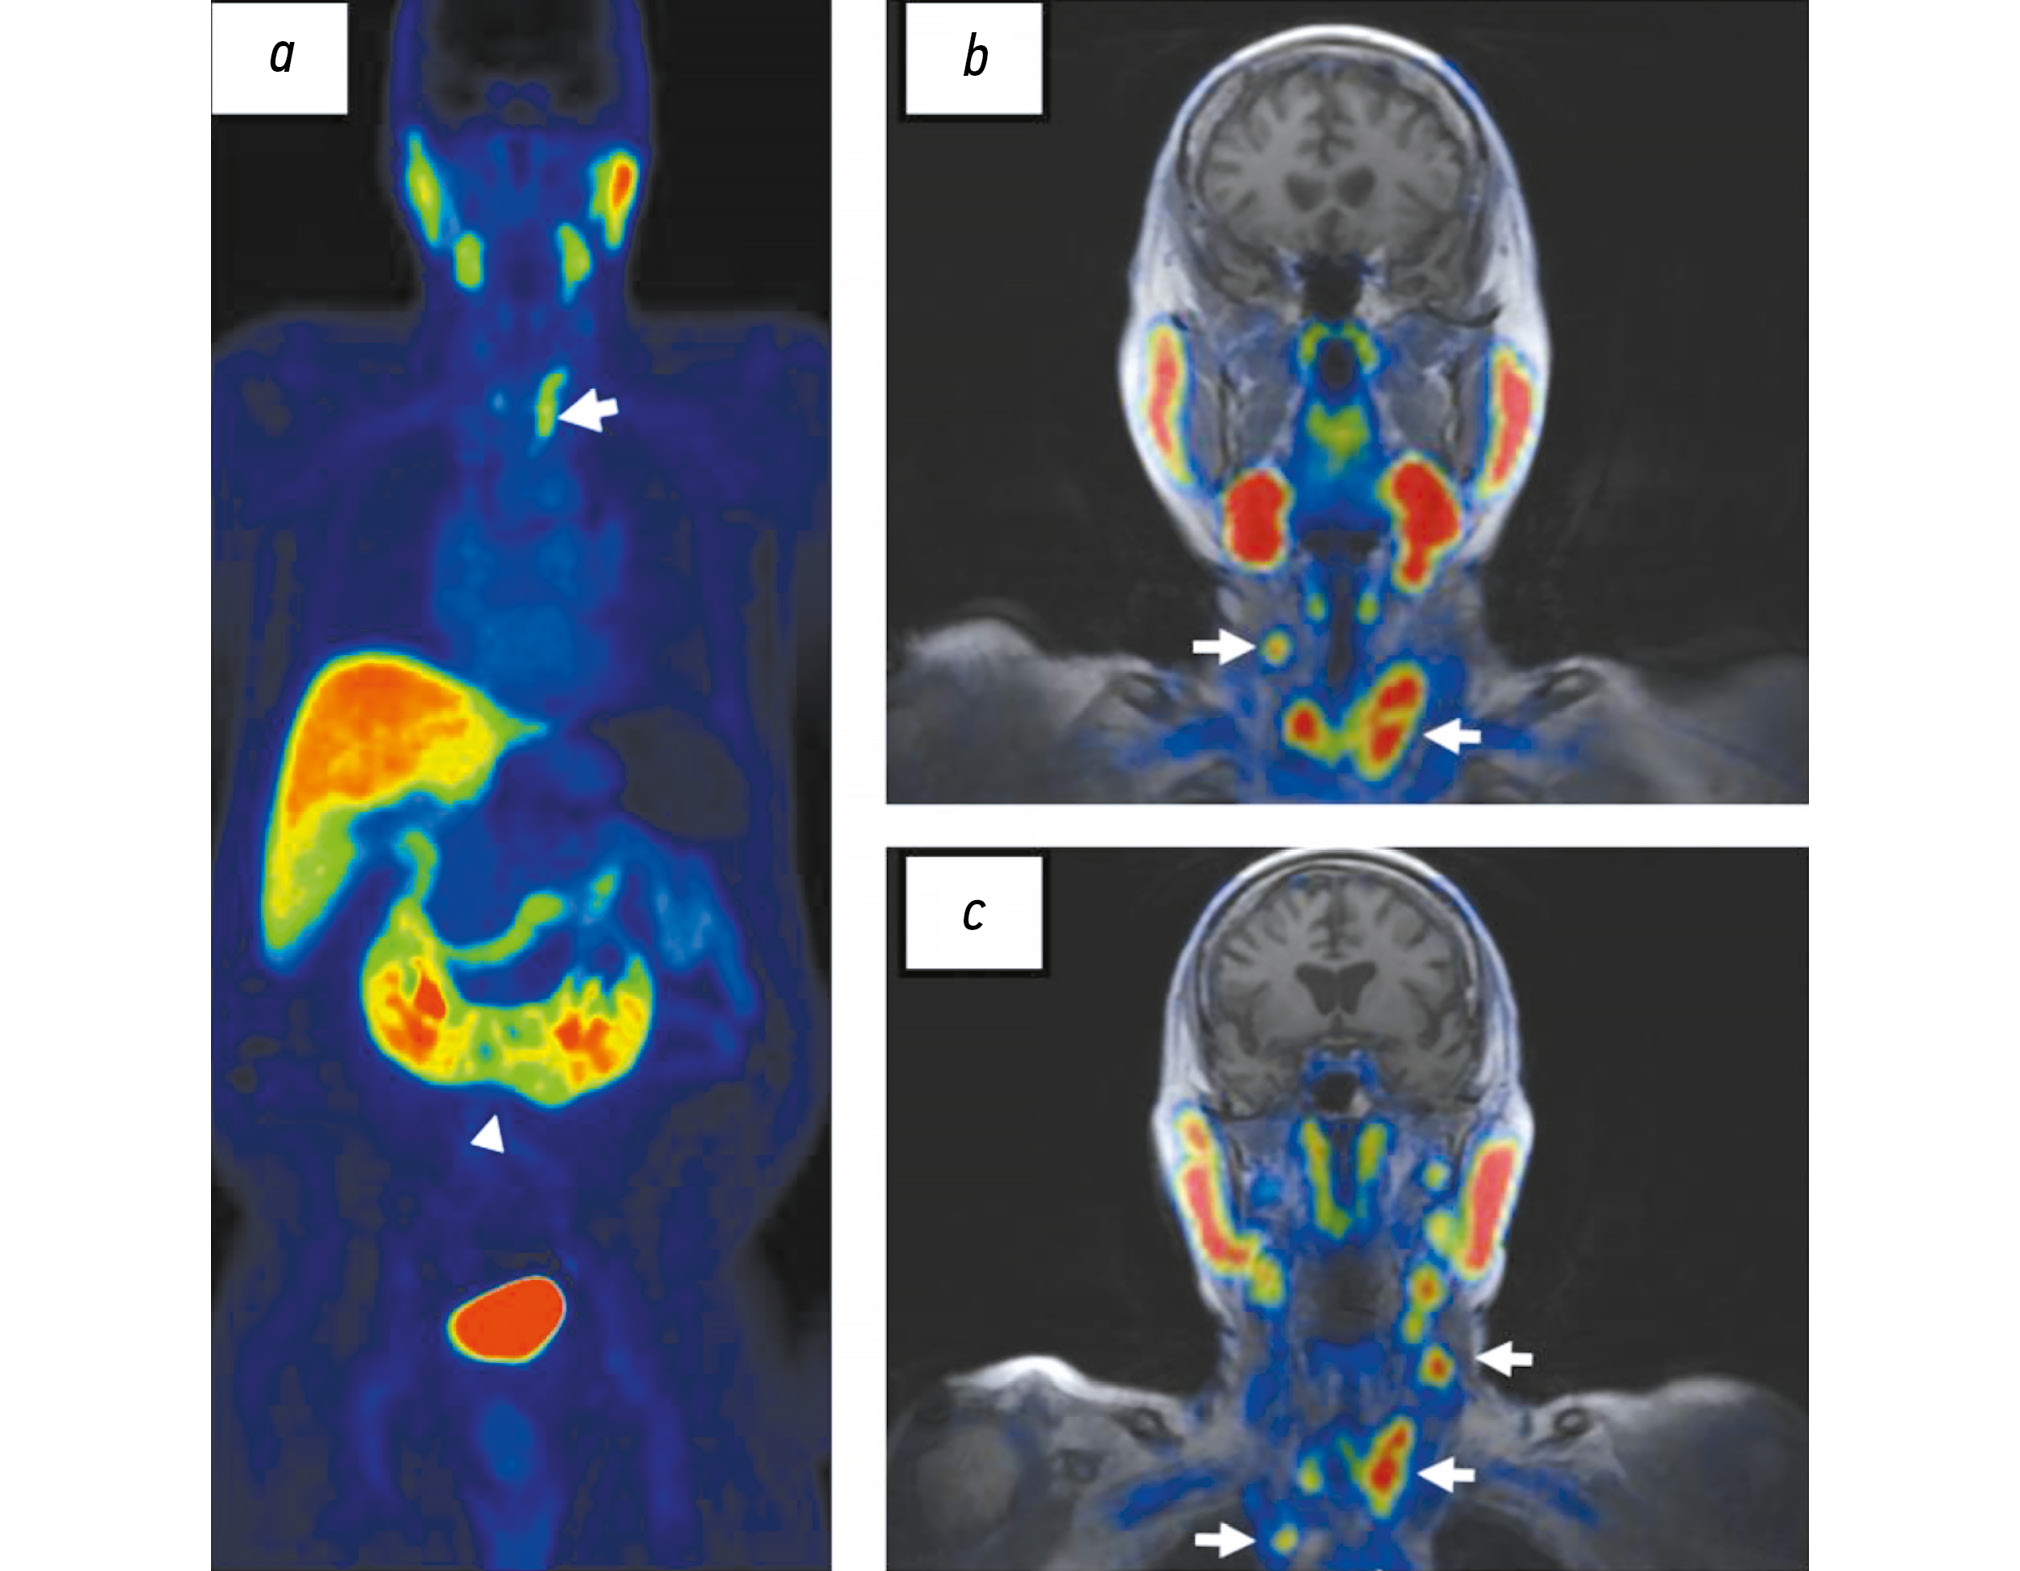

Отдельно надо отметить, что доля ложноположительных результатов при ПЭТ с лигандами ПСМА может достигать 10% [92]. Известны примеры повышения экспрессии ПСМА при опухолях желудка, толстой кишки, почек, щитовидной и молочной желёз, а также в участках воспаления, например при остеомиелите, в зонах консолидирующих переломов. Кроме того, зафиксирована его гиперэкспрессия в некоторых доброкачественных образованиях, таких как гемангиома и фиброзная дисплазия (рис. 5) [53].

Рис. 5. Результаты совмещённой позитронно-эмиссионной и магнитно-резонансной томографии с 18F-простатоспецифичным мембранным антигеном-1007 всего тела, собственное наблюдение: гиперэкспрессия 18F-простатоспецифичного мембранного антигена-1007 в папиллярном раке щитовидной железы и его метастазах в шейных лимфатических узлах (стрелки) у пациента с аденокарциномой предстательной железы (случайная находка); a — наконечником стрелки отмечена подковообразная почка (случайная находка).